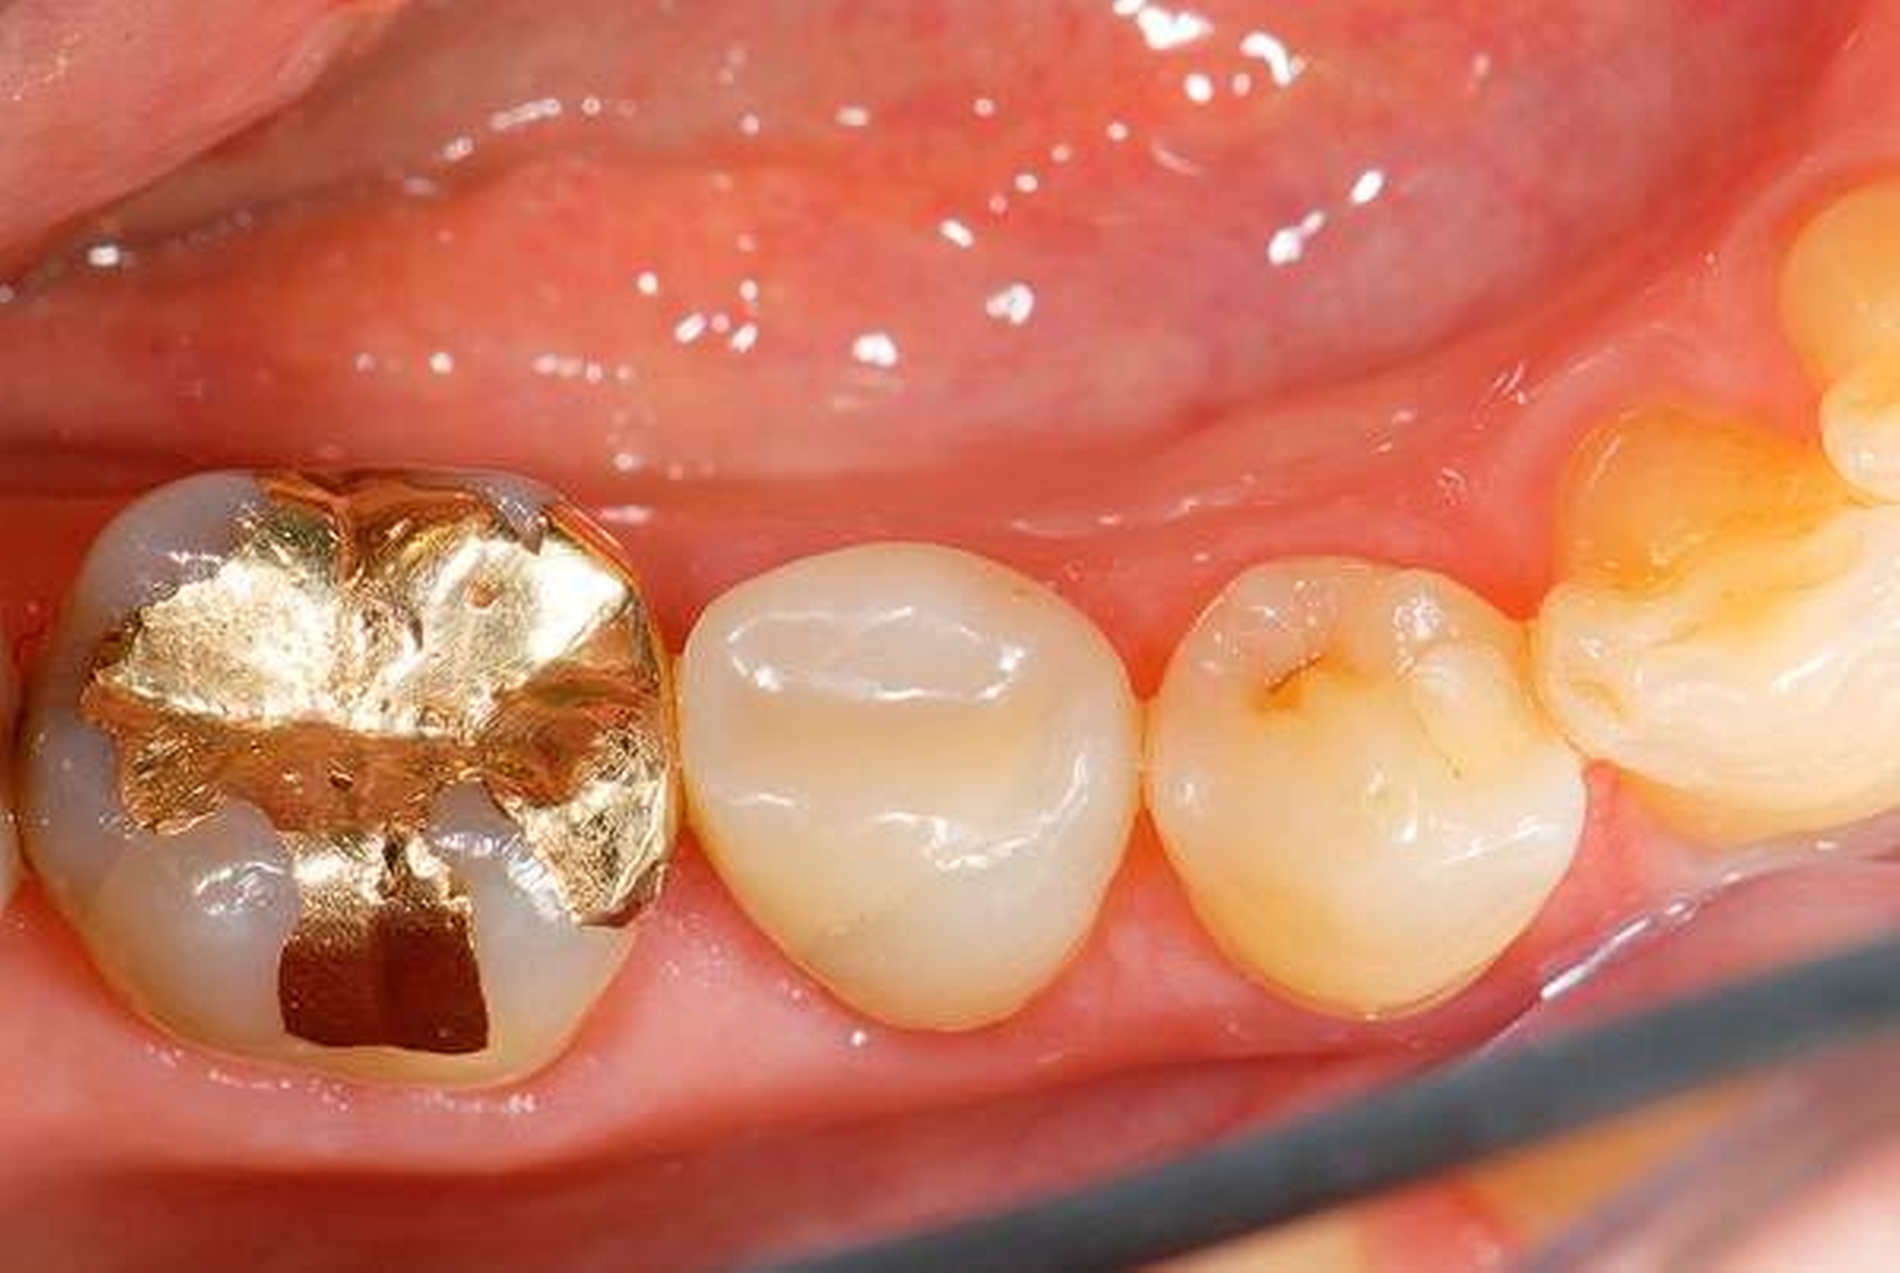

Abbildung 2: Direkte Teilüberkronung im Seitenzahnbereich (R1-Technik)

In den Abbildungen 1 bis 3 werden Optionen für frugale Interventionen auf restaurativem Sektor aufgeführt. Es handelt sich um direkte Vollüberkronungen im Frontzahnbereich (hier: hergestellt in R1-Technik / einphasig) (Abbildung 1), direkte Teilüberkronungen im Seitenzahnbereich (hier: hergestellt in R1-Technik / einphasig) (Abbildung 2), Reparatur-Restaurationen im Seitenzahnbereich (hier: hergestellt in R2-Technik / zweiphasig) (Abbildung 3). Technische Einzelheiten zur Vorgehensweise und den Ergebnissen sind an anderer Stelle beschrieben (Literatur siehe oben).

Für die in Abbildung 2 dargestellte Situation eines tief zerstörten Prämolaren gelten ähnliche Charakteristika. Es gibt in der restaurativen Zahnheilkunde viele Neuerungen, die das Behandlungsspektrum vergrößert haben. Dazu zählen unter anderem: